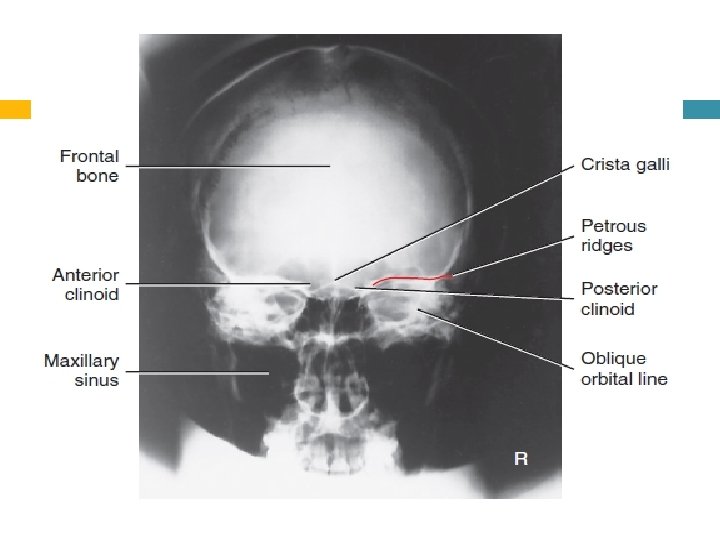

Evaluation Criteria Anatomy Demonstrated: • Frontal bone, crista galli, internal auditory canals, frontal and anterior ethmoid sinuses, petrous ridges, greater and lesser wings of sphenoid, and dorsum sellae are shown. .

Position: • No rotation is evident, as indicated by equal distance bilaterally from lateral orbital margin to lateral cortex of skull. • Petrous ridges fill the orbits and level of the supraorbital margin. • Posterior and anterior clinoids are visualized just superior to ethmoid sinuses. • Collimation to area of interest. Exposure: • Density (brightness) and contrast are sufficient to visualize frontal bone and surrounding bony structures. • Sharp bony margins indicate no motion